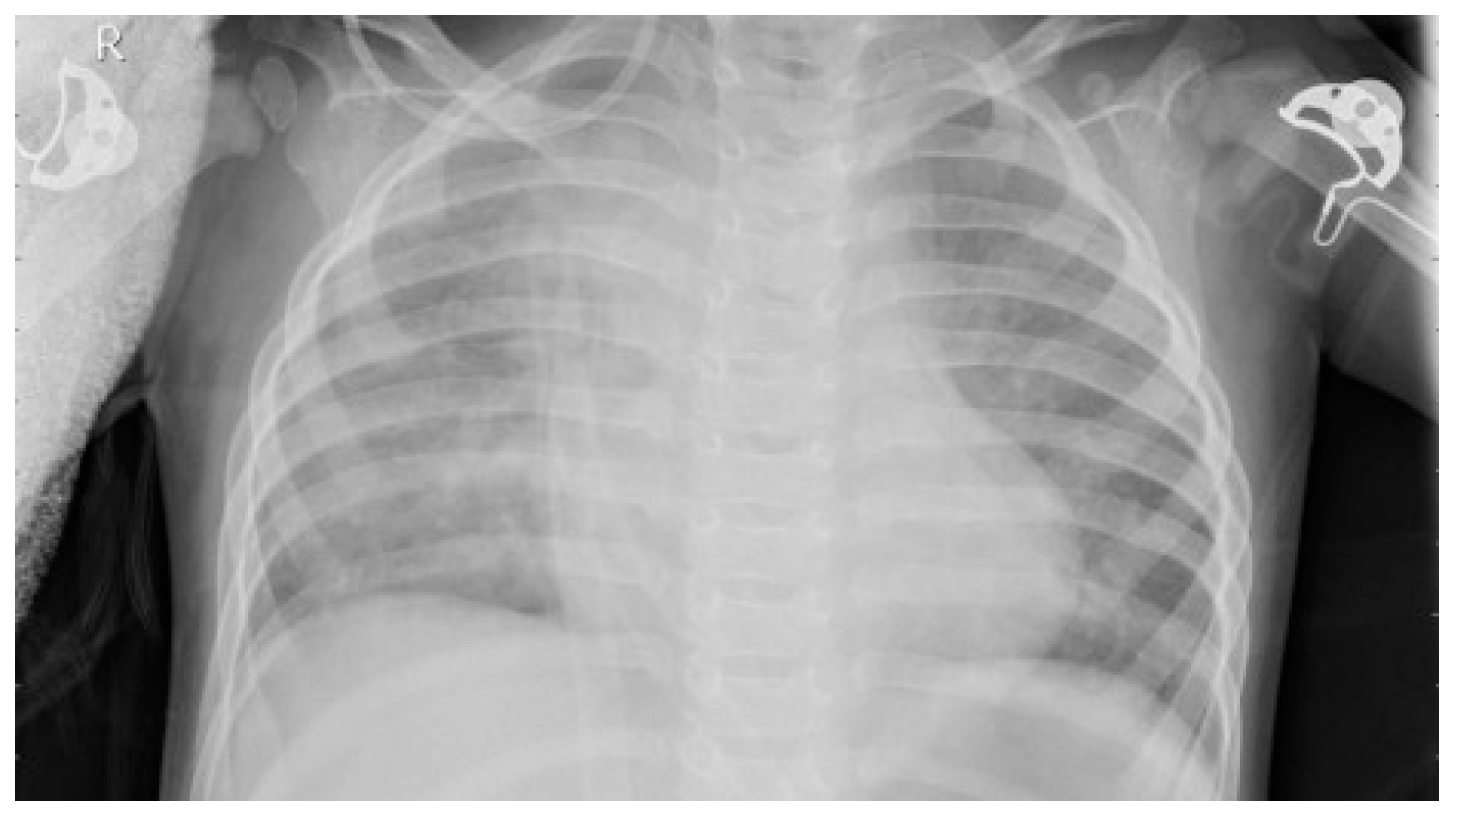

2.2. Dataset

2.4. Image Enhancement Techniques

Resizing